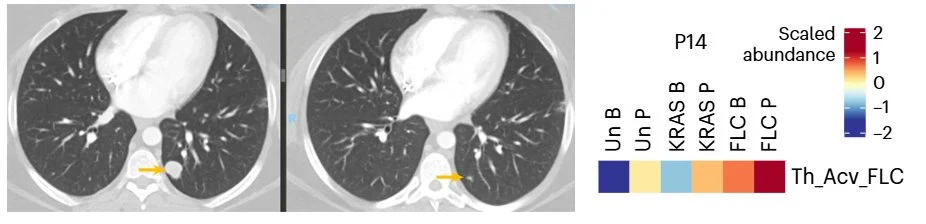

FLC is driven by a currently “undruggable” fusion protein, DNAJ-PKAc. The fusion is intronic → creates a nearly universal neoantigen for FLC We tested a 24aa vaccine spanning the fusion +IPI/NIVO (NCT04248569).

Among 12 patients completing the 10-week priming phase:

9/12 with DNAJ-PKAc T cell responses

3/12 achieved partial responses – 5 pts (all 3 responders and 2 SD pts) in CR years later Responders all had immune responses, suggesting “on-target” vaccine-mediated immunity.